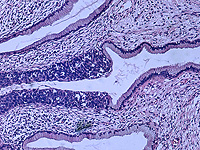

Донор спермы с генной мутацией, радикально повышающей риск развития рака, стал отцом 200 детей по всей Европе. Это выяснилось в ходе масштабного расследования, проведенного крупными вещателями, включая CBS News, BBC News.